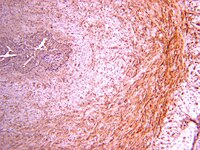

Airway wall remodelling and inflammation are features of chronic asthma. Transforming growth factor beta (TGF-beta) has been implicated in these processes.To determine the effect of allergen challenge on airway inflammation and remodelling and whether TGF-beta isoforms and the Smad signalling pathways are involved.Thirteen patients with atopic asthma underwent inhalational challenge with 0.9% saline, followed by allergen 3-4 weeks later. After both challenges, fibreoptic bronchoscopy was undertaken to obtain bronchial biopsies and tissue samples were processed for immunohistochemistry and examined by microscopy.Forced expiratory volume in 1 s (FEV(1)) fell after allergen challenge (mean (SE) -28.1 (0.9)% at 30 min with a late response at 7 hours (-23.0 (1.2)%). Allergen challenge caused an increase in neutrophils and eosinophils in the bronchial mucosa compared with saline. Sub-basement membrane (SBM) thickness did not change after allergen, but tenascin deposition in SBM was increased. Intranuclear (activated) Smad 2/3 and Smad 4 detected by immunohistochemistry were increased after allergen challenge in epithelial and subepithelial cells of bronchial biopsies. No inhibitory Smad (Smad 7) protein was detected. TGF-beta isoforms 1, 2 and 3 were expressed predominantly in bronchial epithelium after saline and allergen challenges, but only TGF-beta(2) expression was increased after allergen. Double immunostaining showed an increase in TGF-beta(2) positive eosinophils and neutrophils but not in TGF-beta(1) positive eosinophils and neutrophils after allergen challenge.TGF-beta(2) may contribute to the remodelling changes in allergic asthma following single allergen exposure. Full Text Article | Immunohistochemistry | 17251317